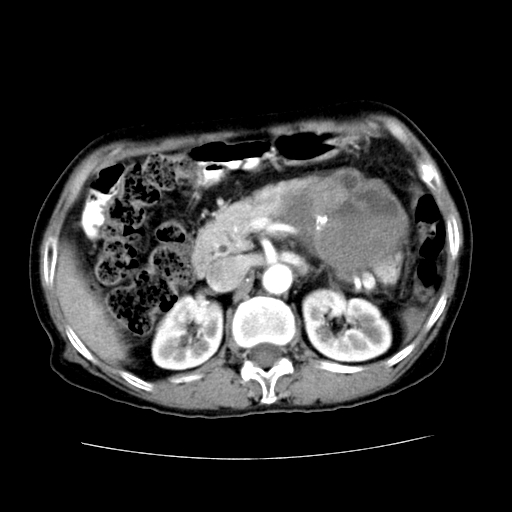

女性,72岁。

主诉中上腹部疼痛不适1年余。

胰腺尾部不规则巨大略低密度肿块,界限清楚,内密度不均,增强动脉期不均匀强化,门脉期明显退减并低于胰腺密度,肿瘤包埋于脾血管。多考虑;来源于胰腺尾部的“胰腺癌”。

1、这个病例确实有点难。影像主要显示胰腺体尾部占位,我们当初也是诊断胰体尾部囊腺癌可能性大,而且读片会上也很多人这么诊断的。

2、手术所见:打开腹腔发现胃与胰腺体尾部可见肿块,大小约10×8×11cm,质硬,不可推动,周围血供丰富。术中诊断:胃肿瘤侵及胰腺体尾部。

1)、胃小弯侧胃肠间质瘤(考虑恶性),瘤体大小13.5×7×6.5cm,上下切缘阴性。

2)、胃小弯1只、幽门下2只淋巴结慢性炎。免疫组化:cd117(+)、cd34(+)、sma(+)、desmin(-)、s-100(-)、ki-67<10%(+).

4、这个肿瘤太大了,而且密度不均性强化,从这点我们应该不能单纯诊断胰腺癌,而应想到目前流行的胃肠道间质瘤。这个肿瘤主要发生于胃壁浆膜层,所以显示与胃壁关系不是很紧密,故而大多认为是胰腺癌。